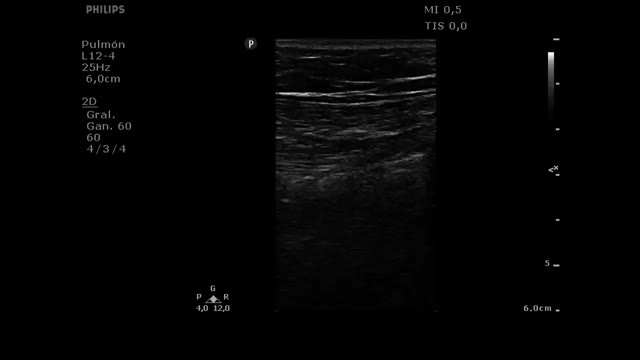

Ultrasound as a tool guiding the management of patients with respiratory failureIntubationThe usefulness of ultrasound in intubation includes both evaluation of the upper airway to predict a difficult airway,13,14 and confirmation of correct positioning of the endotracheal tube (ETT) after intubation.15,16 We will focus on this latter aspect, since emergent intubation is one of the most common scenarios in the critical patient, where in most cases the airway cannot be evaluated before intubation.

Confirmation of intubationConfirmation of correct positioning of the ETT is crucial, since it has been estimated that 3.3% of all emergent intubations place the tube in the esophagus.17

Tracheal ultrasound has been shown to be as useful as capnography in excluding esophageal intubation, with a sensitivity of 98.7% and a specificity of 97.1%, and it performs even better in patients with low cardiac output in the context of cardiac arrest.18 Furthermore, tracheal ultrasound offers the advantage of not needing the start of ventilations for confirmation (in contrast to capnography), thus reducing the risk of gastric distension and bronchoaspiration.

In order to discard esophageal intubation we need to use a high-frequency linear transducer located at the suprasternal notch, obtaining an anterior transverse image of the neck and airway. In this plane, the trachea is identifies as a hyperechogenic inverted U-shaped line generated by the mucosa-airway interface, with a typical posterior acoustic shadow artifact (Fig. 4). The esophagus is collapsed and in a left lateral paratracheal position. Esophageal intubation would be detected by the observation of an anechoic circular structure adjacent to the trachea (generally on the left side of the trachea) - a sign known as “double trachea” (Fig. 4).